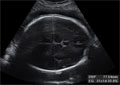

En la ecografía 2D del tercer trimestre de embarazo se puede hacer la medición del diámetro biparietal, que es la distancia que existe entre los huesos parietales del cráneo. Esta medida es una buena referencia del crecimiento fetal. En la imagen, esta medida aparece acotada por una línea discontinua.

Ecografía de la medición del diámetro biparietal